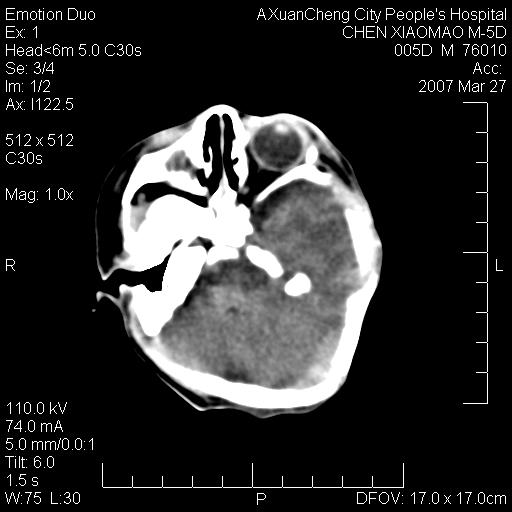

大家看看可有出血?另外枕骨中央是骨缝还是骨折

大家看看可有hie ?还有左侧枕部胡形高密度ct为45~53hu,可有硬膜下血肿?

左颞枕部有出血,枕骨有骨折

未见明显异常,,那是横窦影,“缝”是后囟